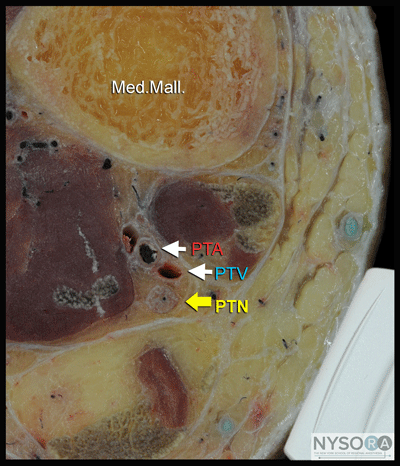

![]() Figure 2: Cross-sectional anatomy of the posterior tibial nerve at the level of the ankle. Shown are posterior tibial artery (PTA) and vein (PTV) behind the medial malleolus (Med. Mall.) The posterior tibial nerve (PTN) is just posterior and superficial to the posterior tibial vessels. General Considerations Using an ultrasound-guided technique affords a practitioner the ability to reduce the volume of local anesthetic required for ankle blockade. Because the nerves involved are located relatively close to the surface, ankle blocks are easy to perform technically; however, knowledge of the anatomy of the ankle is essential to ensure success. Ultrasound Anatomy Ankle block involves anesthetizing five separate nerves: 2 deep nerves and 3 superficial nerves. The 2 deep nerves are tibial (TN) and deep peroneal nerve (DPN). The superficial nerves are superficial peroneal, sural and saphenous. All nerves except saphenous nerve are terminal branches of the sciatic nerve; saphenous nerve is a cutaneous extension of the femoral nerve. Tibial Nerve The tibial nerve is the largest of the five nerves at the ankle level and provides innervation to the heel and sole of the foot. With a linear transducer placed transversely at (or just proximal to) the level of the medial malleolus, the nerve can be seen immediately posterior to the posterior tibial artery (Figures 1, 2, and 3A and B). Color Doppler can be very useful in depicting the posterior tibial artery when it is not readily apparent. The nerve typically appears hyperechoic with dark stippling. A useful mnemonic for the relevant structures in the vicinity is Tom, Dick ANd Harry, which refers to, from anterior to posterior, the tibialis anterior tendon, flexor digitorum longus tendon, artery/nerve/ vein, and flexor hallucis longus tendon. These tendons can resemble the nerve in appearance, which can be confusing. The nerve's intimate relationship with the artery should be kept in mind to avoid misidentification.